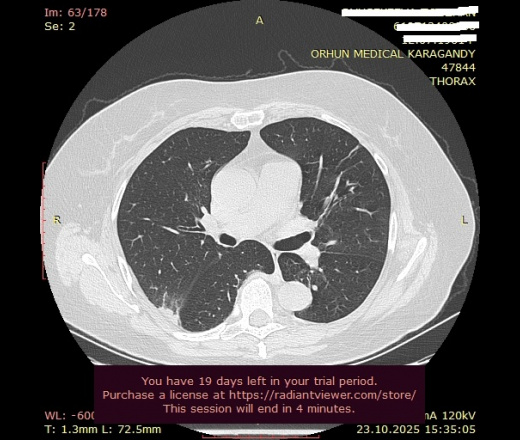

Может ли данный очаг (ТЭЛА?): "В верхней доле (S2) правого легокого, субплеврально по задней поверхности, участок уплотнения инфильтративного характера, плотностью 9HU, неправильной формы, размерами 3,2х0,7х4,8 см, с нечеткими неровными контурами, с признаками частичной консолидации легочной ткани" - вызвать то расширение легочного ствола, который Вы заметили?

Добрый день, уважаемый Мурат Максутович! Если коротко, то - может. А если описать данные изображения, как "участок субплевральной консолидации с нечеткими контурами, основанием прилежащей к плевре, перифокальное "матовое стекло", наличие бронхососудистых тяжей", так рука сама собой выведет "КТ-картина в большей степени соответствует ТЭЛА и инфаркту легкого (инфаркт-пневмонии), рек УЗИ вен нижних конечностей, КТ ОГК с в/в КУ), но вся эта стройная картина также может как подтвердиться, так и рассыпаться в результате дообследования

Второй версией предполагал инфарктную пневмонию, так как тоже отметил расширенный легочной ствол (опять же, визуально, так как замерить нет возможности без DICOM), но меня смутило то, что при ТЭЛА всё-таки прослеживается принадлежность изменений к сегментам, а здесь на границе междолевой плевры, что более характерно для воспалительных изменений.

Коллеги, а слева ближе к корню тоже свежая консолидация?

Нет, это анатомические структуры (сосуды).